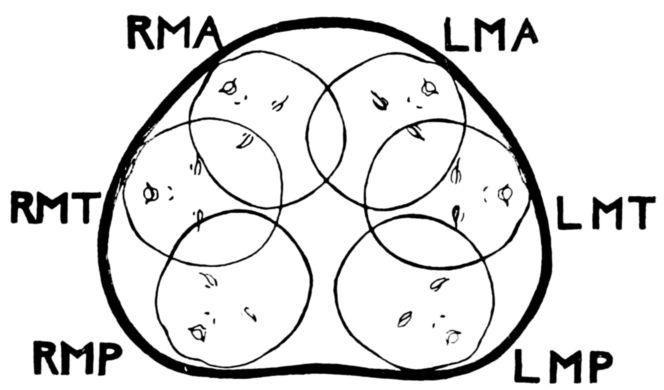

| 54. | Diagram of six positions in a vertex presentation | 222 |

| 55. | Diagram of six positions in a face presentation | 223 |

| 56. | Diagram of six positions in a breech presentation | 223 |

| 61. | Diagrams showing positions of nurse’s hands in four maneuvers of abdominal palpation | 229 |